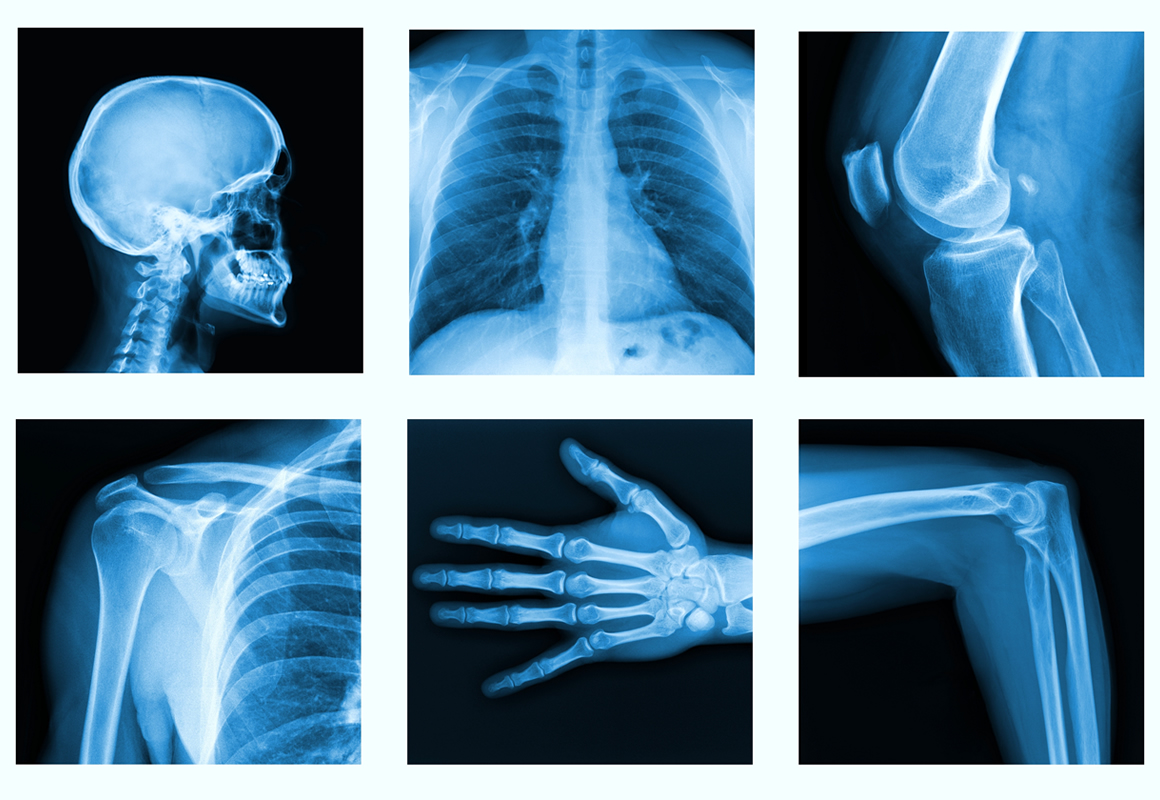

Radiology Wallpapers - Wallpaper Cave

wallpapercave.comradiology wallpaper wallpapers footage organe pond5 innere stock backgrounds desktop wallpapersafari full

wallpapercave.comradiology wallpaper wallpapers footage organe pond5 innere stock backgrounds desktop wallpapersafari full

Fisioterapia Traumatológica - Sananova

sananova.esX-ray Wallpapers - Wallpaper Cave

sananova.esX-ray Wallpapers - Wallpaper Cave

wallpapercave.comwallpaper ray wallpapers radiology bone xray background desktop hd cracking knuckle mystery cracks math breakdown needs bit building first getty

wallpapercave.comwallpaper ray wallpapers radiology bone xray background desktop hd cracking knuckle mystery cracks math breakdown needs bit building first getty

www.pxfuel.comRadyoloji, Radyografi HD Duvar Kağıdı | Pxfuel

www.pxfuel.comRadyoloji, Radyografi HD Duvar Kağıdı | Pxfuel